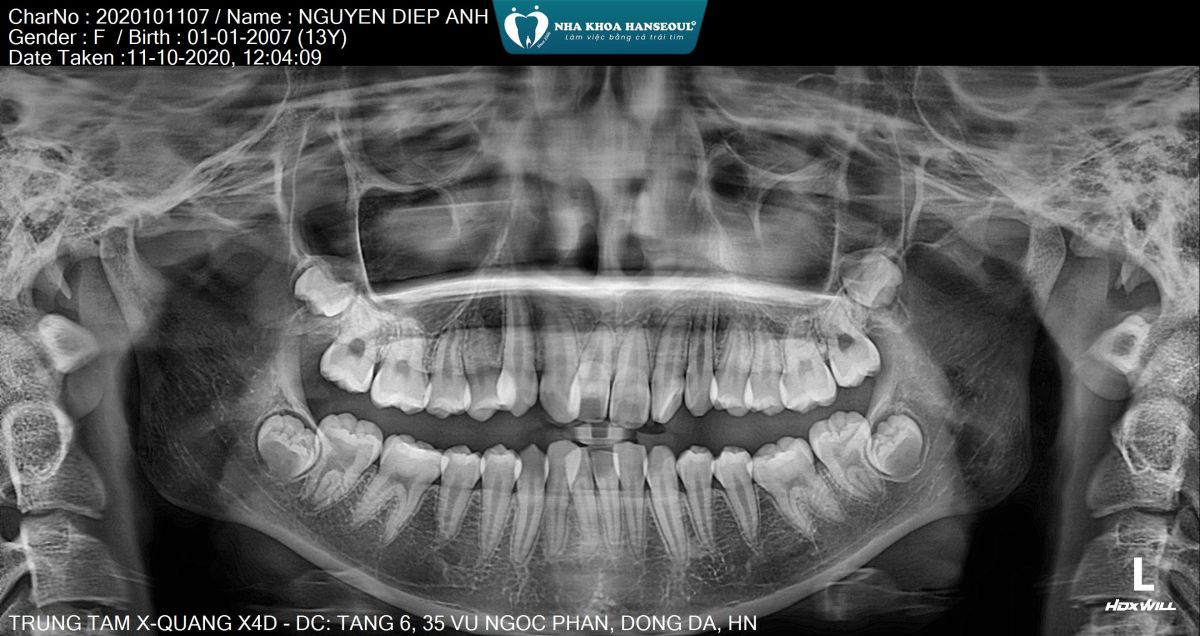

Bác sĩ chỉnh nha chuyên sâu trực tiếp xây dựng phác đồ dựa trên phim X-quang, hình ảnh 3D và phân tích khớp cắn, đảm bảo răng di chuyển đúng hướng – đúng lực – đúng thời điểm.

Kết quả sau niềng - Màn "lột xác" ấn tượng

- Sau khi tháo niềng, Diệp Anh thay đổi rõ rệt:

- Răng thẳng hàng, không còn chen chúc

- Khớp cắn chuẩn – ăn nhai tự nhiên

- Khuôn mặt cân đối, góc nghiêng hài hòa hơn

- Nụ cười rạng rỡ – tự tin trong giao tiếp, chụp ảnh